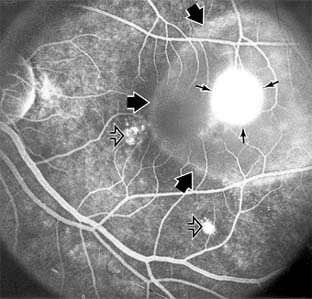

Figure 10-1

Figure 10-1: Age-related macular degeneration with discrete (small arrow) and large confluent (large arrow) macular drusen.